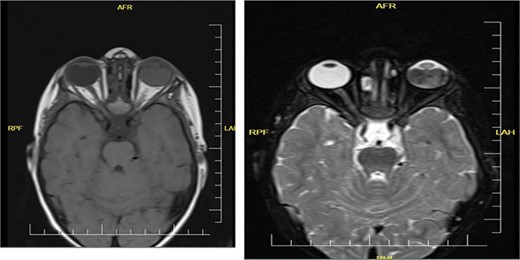

The laboratory examination’s results revealed a low hematocrit of 27 and a low hemoglobin (HB) of 8.5 mg/dl. Orbital ultrasonography revealed a hyper-echogenic tumor in the left eye with vitreous seeding (Fig. 2), while the orbital MRI showed a left intraocular mass of 10.10 mm by 8.7 mm with medium intensity in T1W/FLAIR sequences and a low intensity in T2W images (Fig. 3). The lesion has a slightly heterogeneous contrast enhancement in the post-contrast sequence with group D international classification of Rb (ICOF) stage I. The radiological findings most likely indicated Rb. Tumors occupied 50% of the globe, but there was no subretinal detachment. Fortunately, the tumor has not affected the optic nerve. An enucleation procedure (removal of the whole contents of the eye) under general anesthesia was performed (Fig. 4). Histopathological examination showed hyperchromatic small round blue cells with scant cytoplasm arranged in sheets, nests, and Flexner–Wintersteiner rosettes with histologic G3 with endophylitis, tumor necrosis, and calcification (35% of calcification is eosinophilic) that was consistent with Rb (Fig. 5). After 3 months of follow-up in the outpatient department, a prosthetic eye was implanted for cosmetic purposes (Fig. 6).

Coronal orbital MRI of t1 and t2 shows left intraocular tumor with vitreous seeding.